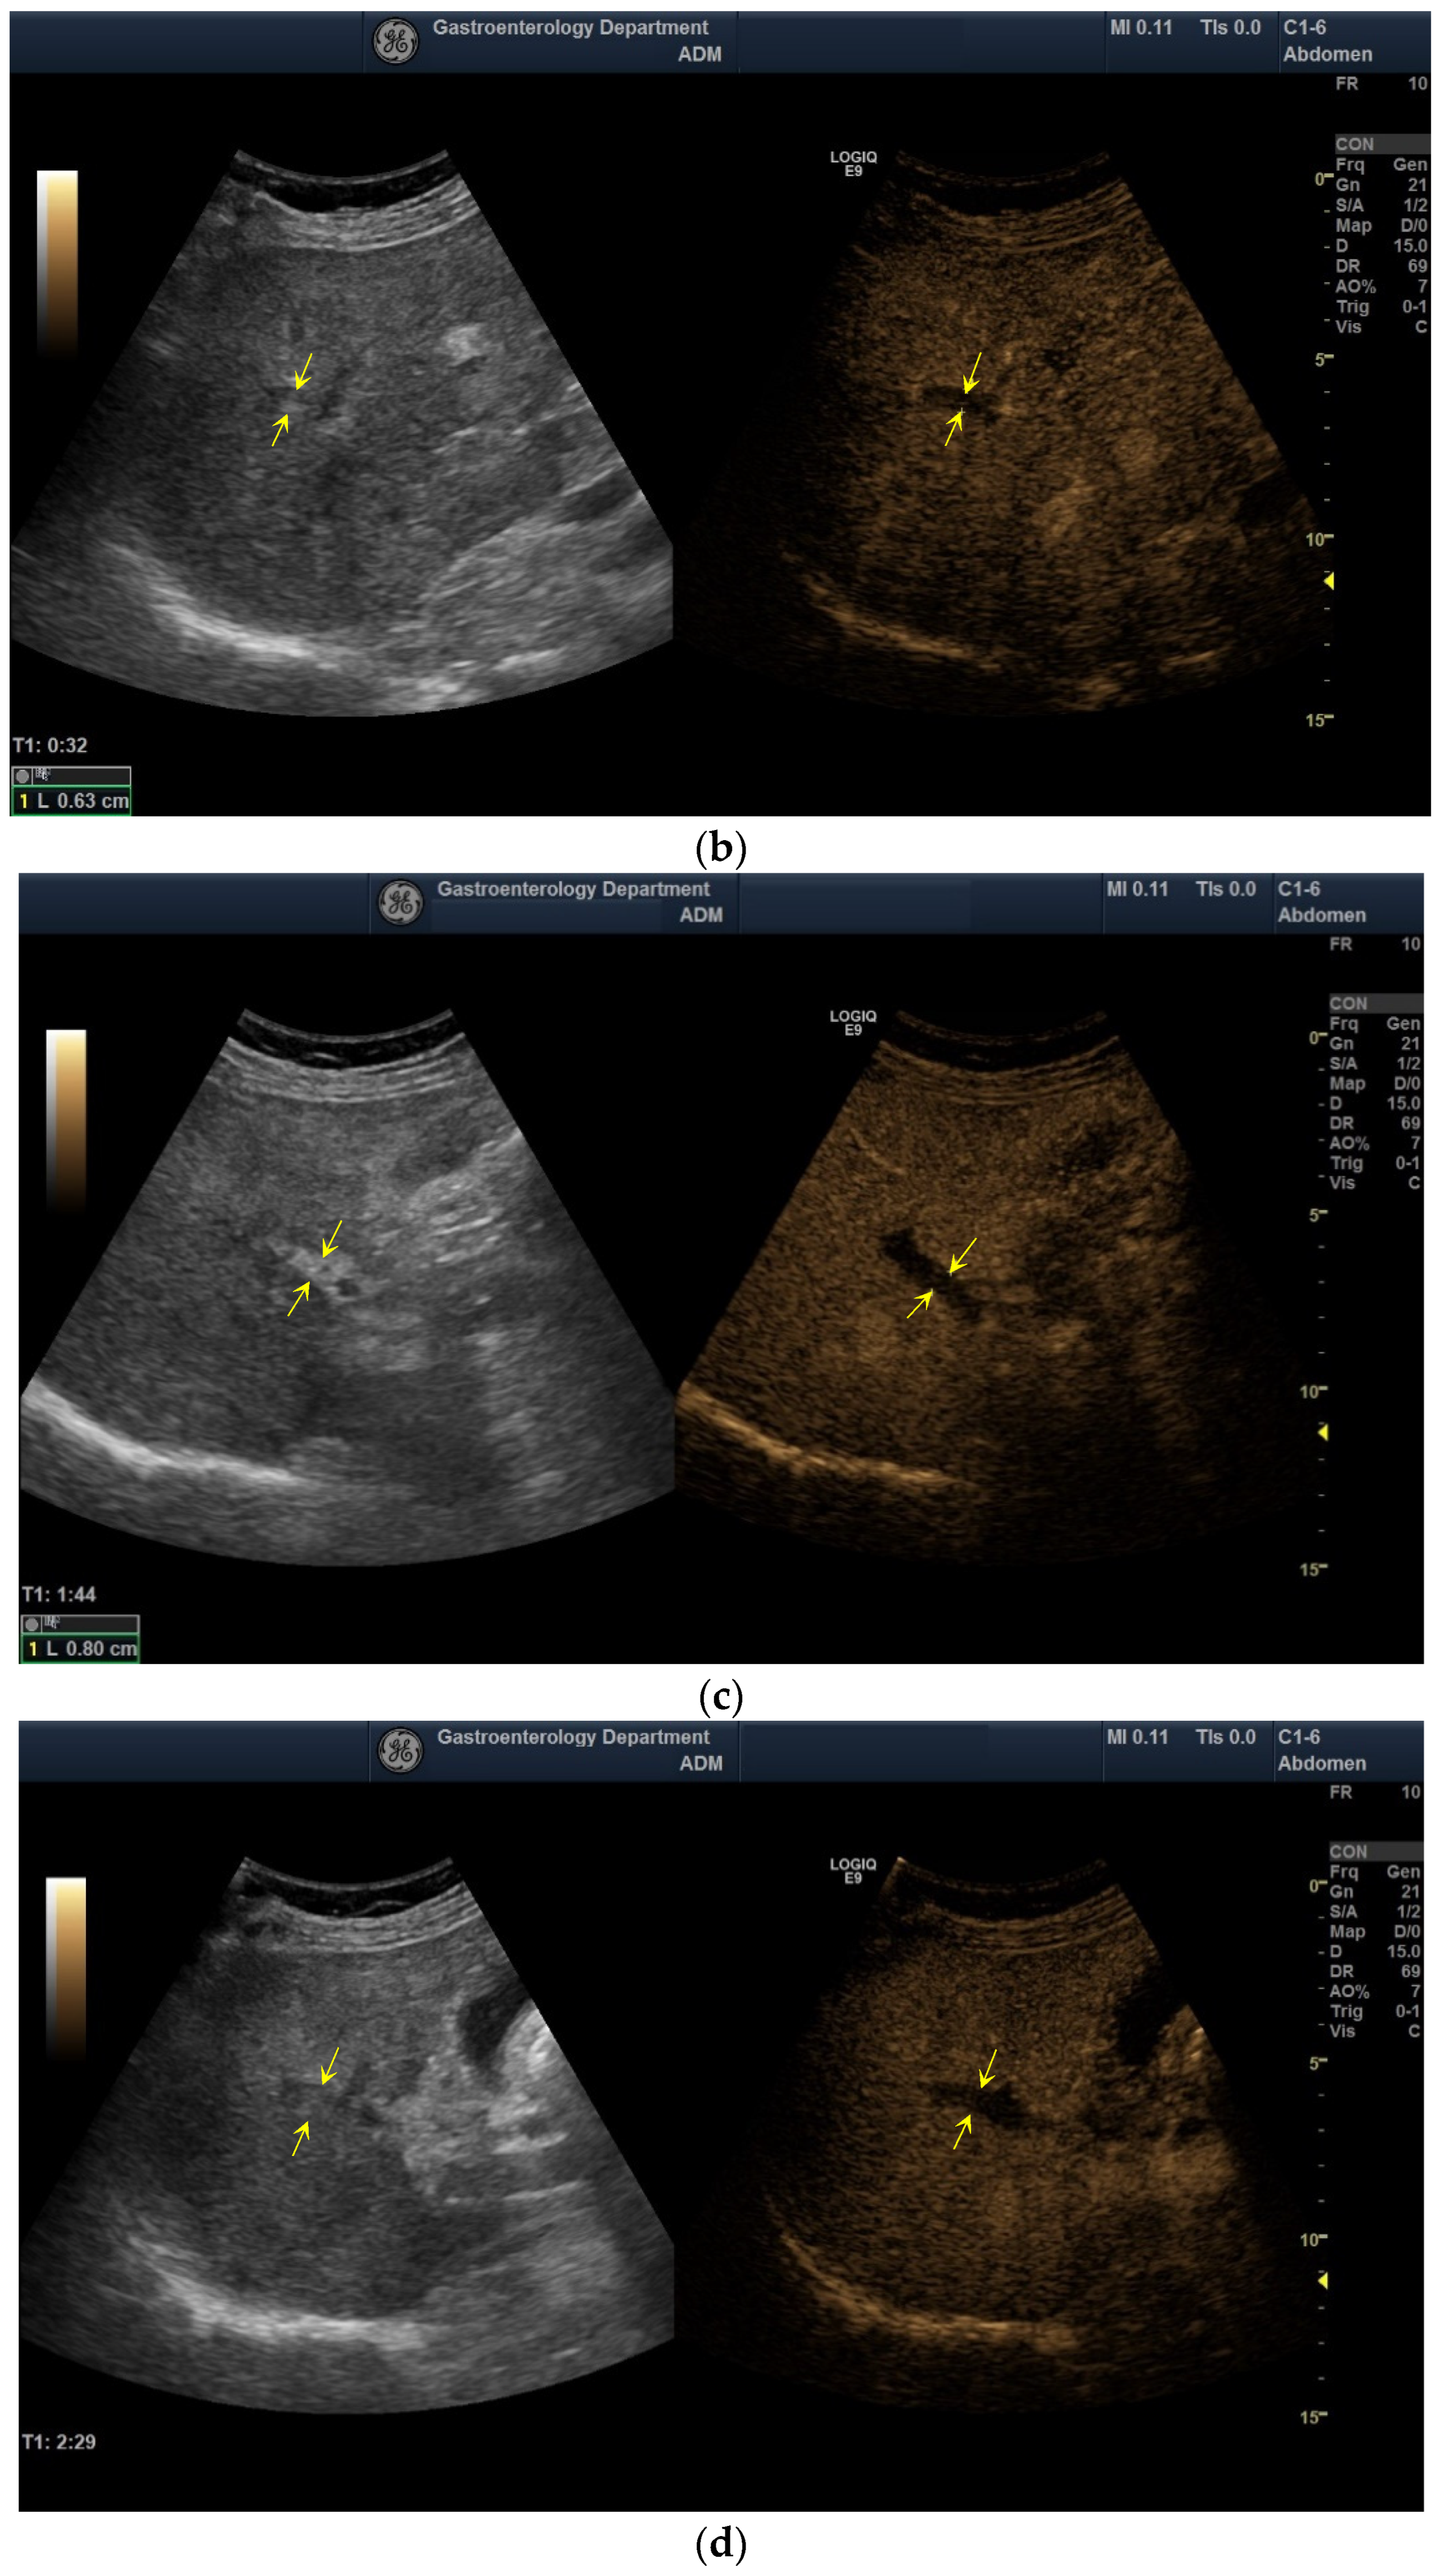

2.3. Diagnostic of PVT

3.5. The Performance of CEUS for the Characterization of PVT